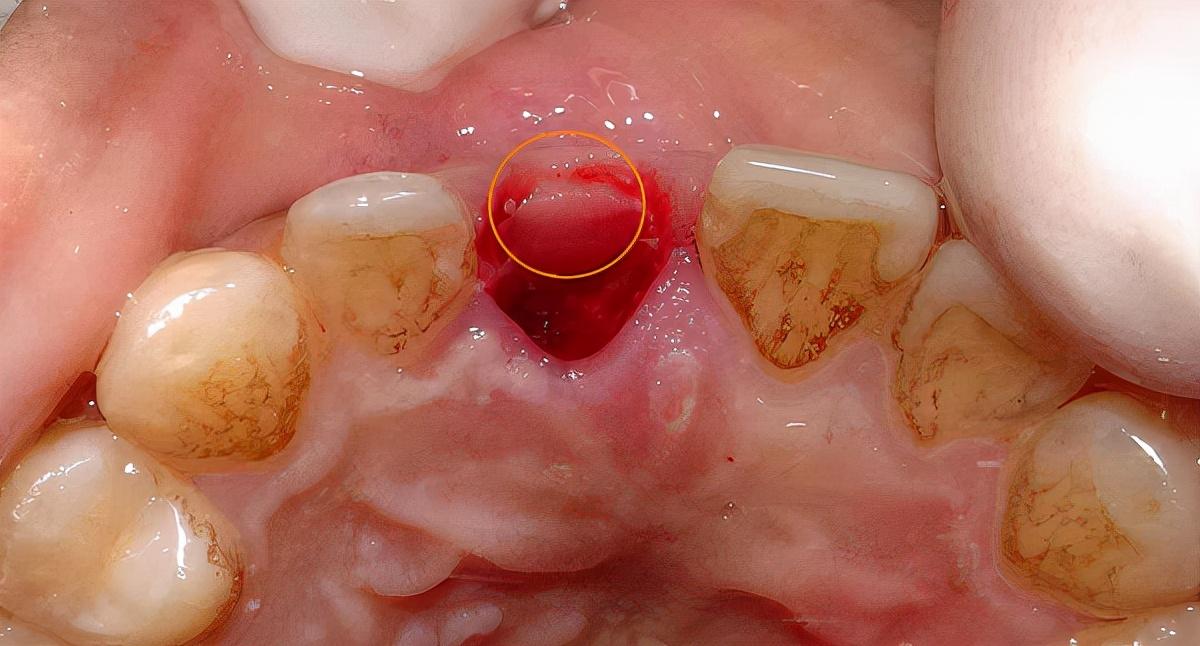

口內(nèi)照:

拔牙的時(shí)候,看具體患者的情況。如果不飽滿,需要支撐,也可以做盾構(gòu)術(shù)。留一部分牙片,支撐作用,后期美學(xué)果好。